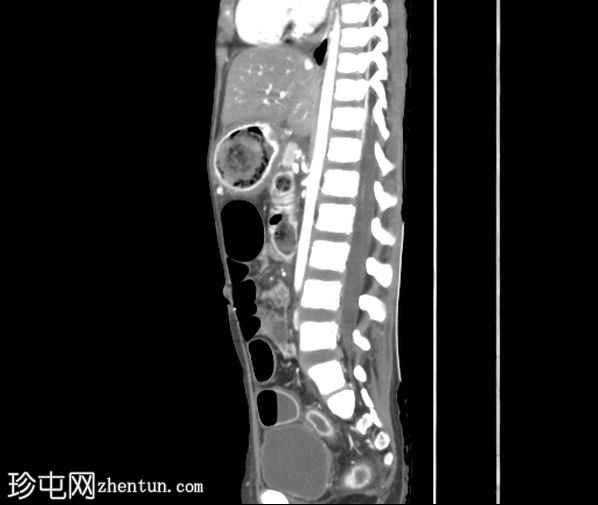

矢状位增强扫描(门静脉期)

胃腔内可见巨大肿块,内含斑驳状软组织、气体和高密度灶,延伸至幽门、十二指肠和近端空肠(长发公主综合征)。十二指肠轻度扩张。

胃壁强化减弱及胃壁积气区域。